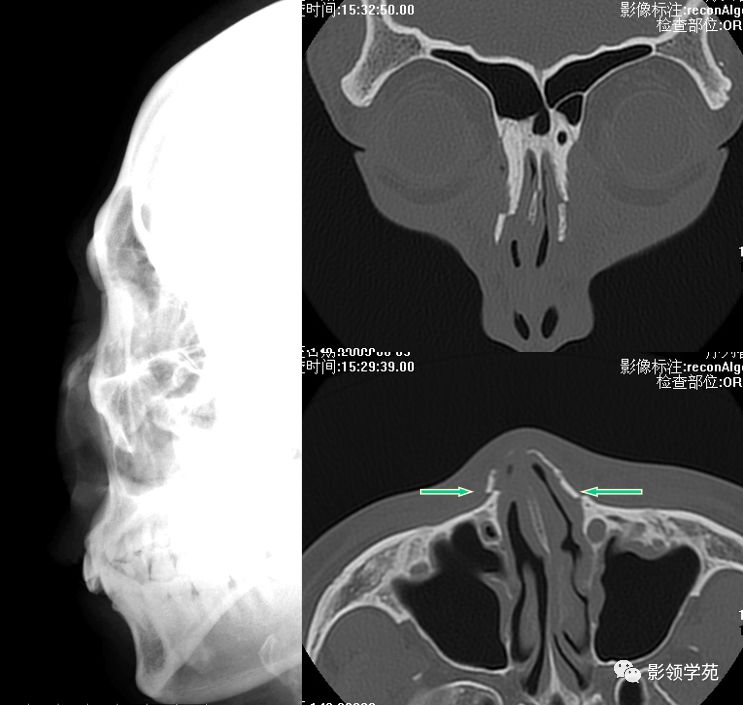

X线平片:侧位

HRCT

- 横断面:听眶下线

- 冠状面:鼻骨长轴平行线

- 层厚:1~2mm

鼻骨正常侧位

鼻骨横断面HRCT

鼻骨冠状面HRCT

骨折HRCT表现

- 外形

- 骨折线

- 软组织肿胀、积气

- 邻近部位骨折

双侧鼻骨骨折

双侧上颌骨额突骨折

鼻中隔骨折